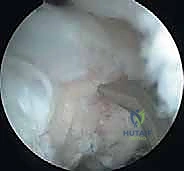

الخطوة 3: الاستكشاف التشخيصي (Diagnostic Sweep)

يتم إدخال المنظار لفحص المفصل بالكامل من الداخل. يتم تقييم حالة الغضروف، البحث عن أي أجسام حرّة مختبئة، وتقييم مدى تلف الرأس الصغير (Capitellum).

- أ. إزالة الأجسام الحرة وتنظيف المفصل (Debridement):

إذا كانت القطعة منفصلة تماماً وميتة ولا يمكن إنقاذها، يتم استخراجها بالكامل لمنعها من تدمير بقية المفصل. يتم تنظيف حواف